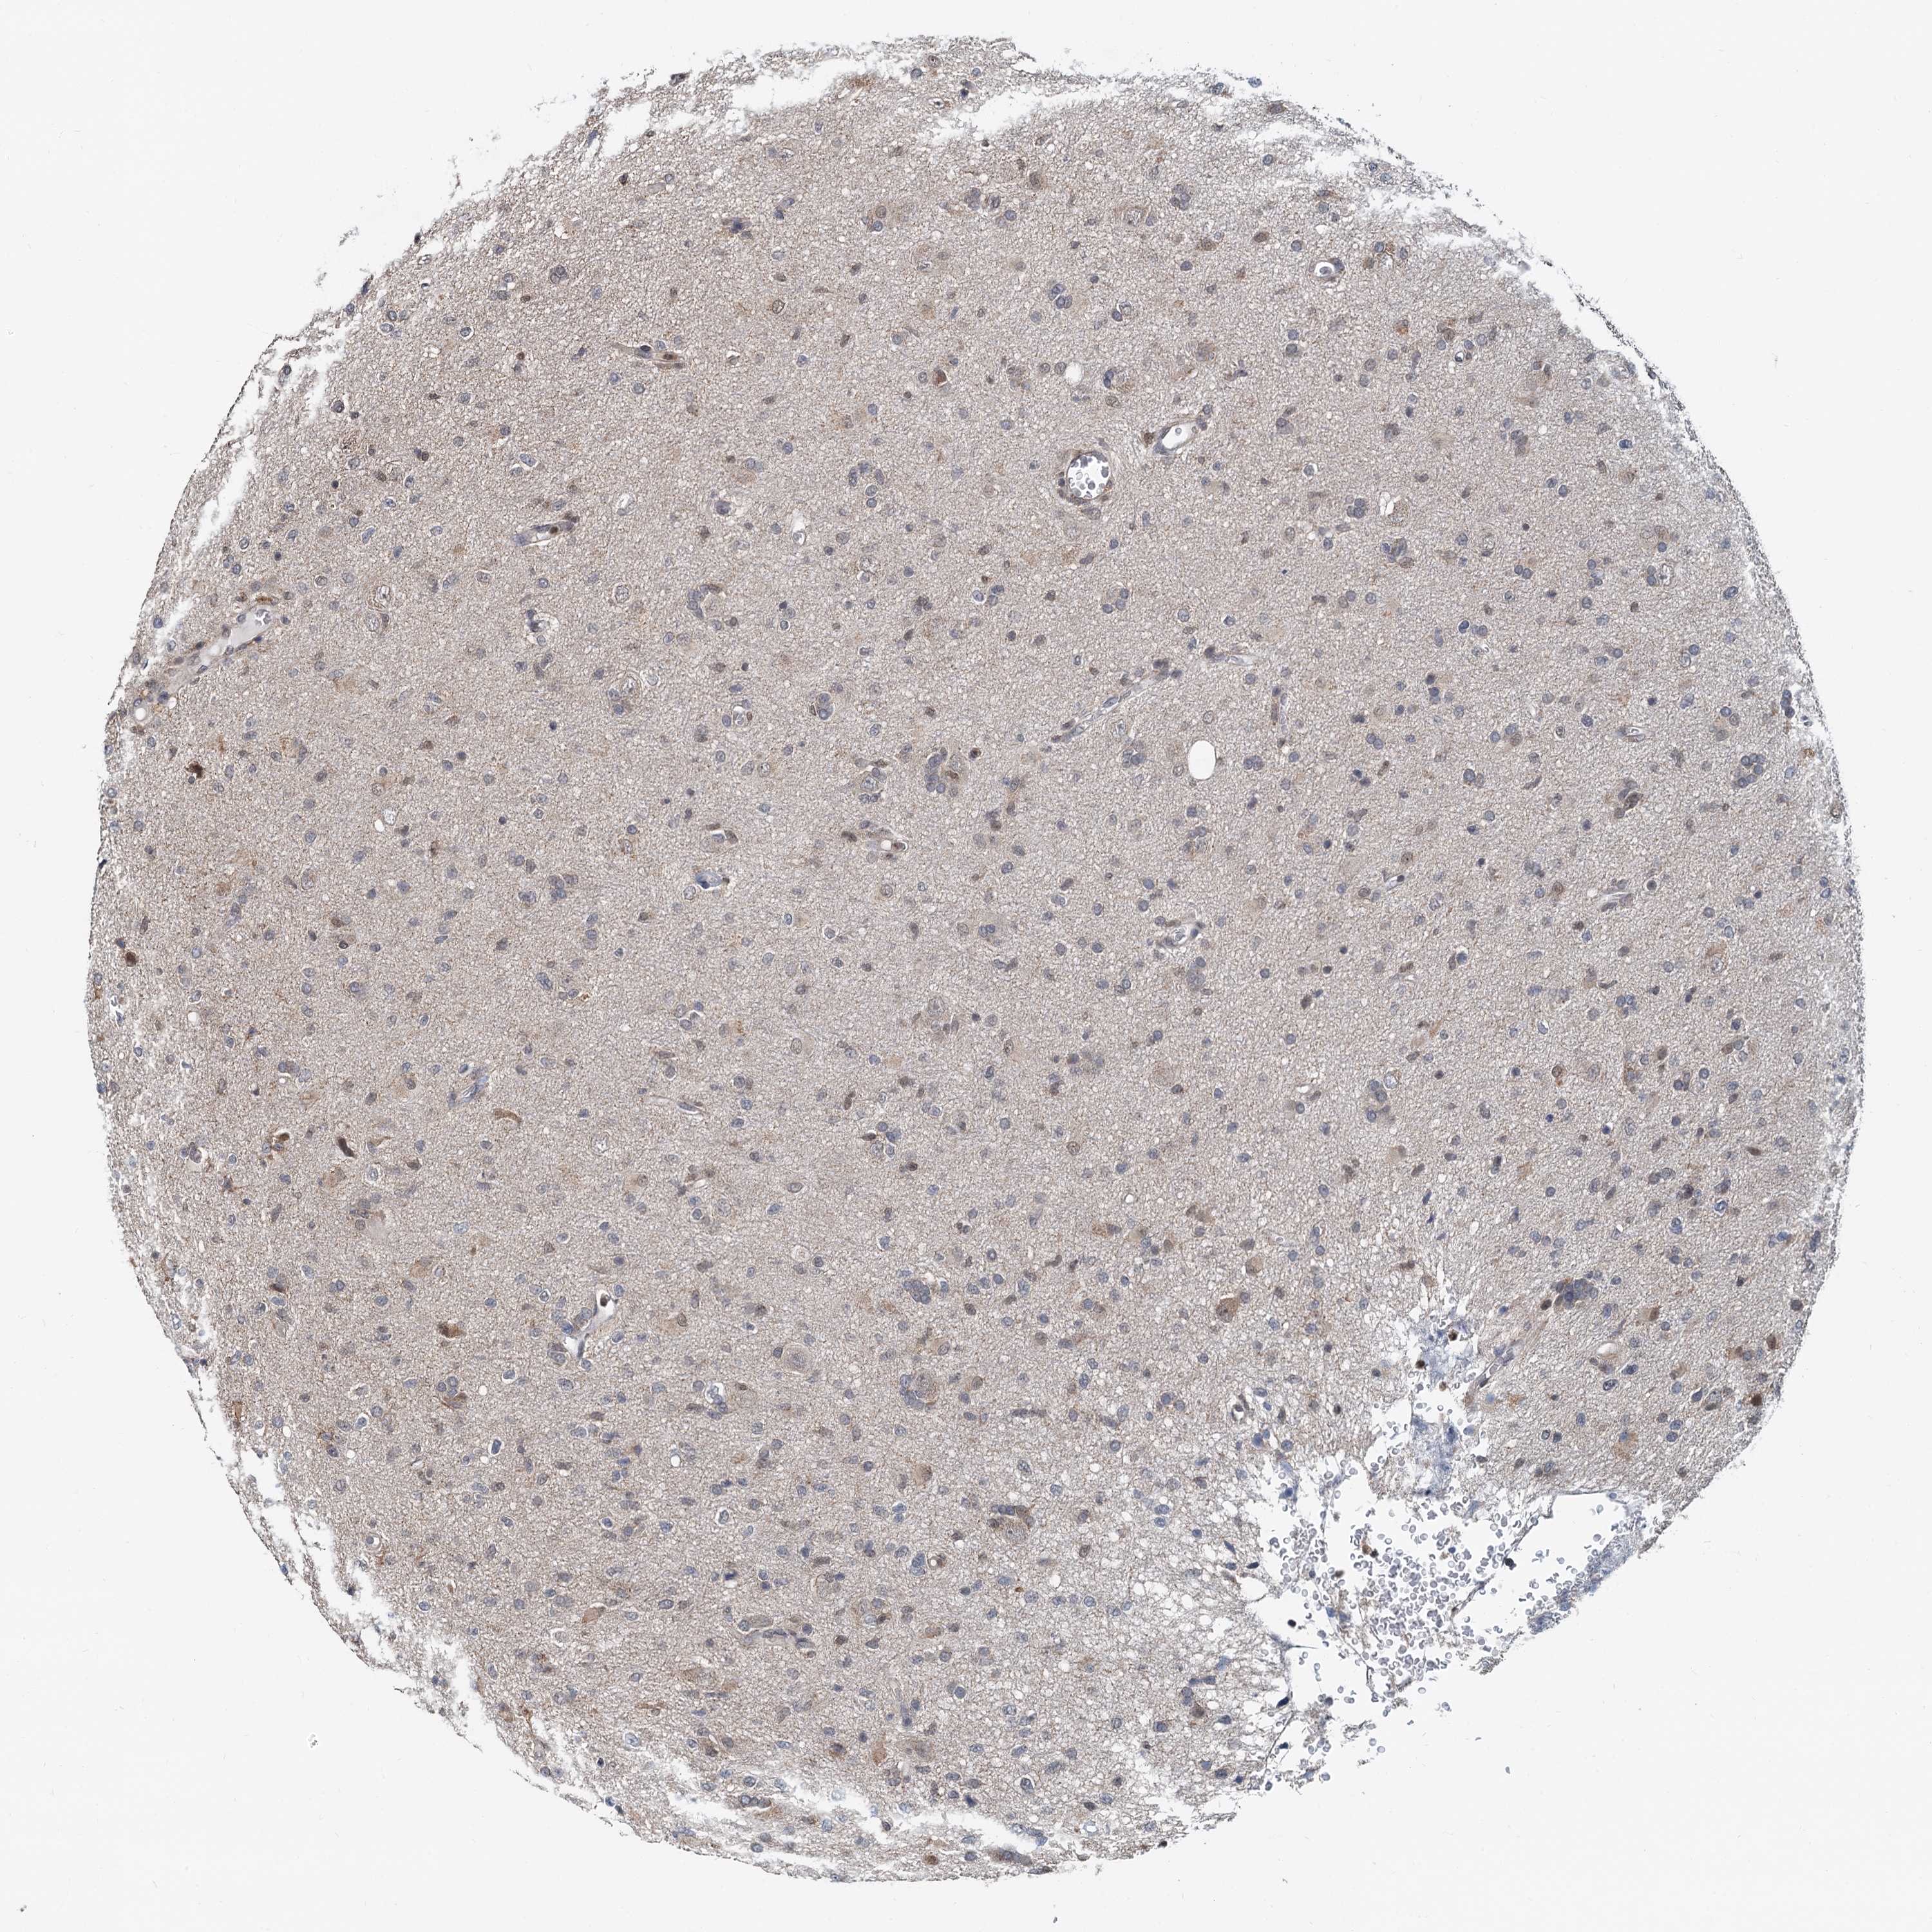

GLIOMA - Protein expressioni

A mouse-over function shows sample information and annotation data. Click on an image to view it in a full screen mode. Samples can be filtered based on level of antibody staining by selecting one or several of the following categories: high, medium, low and not detected. The assay and annotation is described here.

Note that samples used for immunohistochemistry by the Human Protein Atlas do not correspond to samples in the TCGA dataset.

Antibody stainingi

Antibody staining in the annotated cell types in the current human tissue is reported as not detected, low, medium, or high, based on conventional immunohistochemistry profiling in selected tissues. This score is based on the combination of the staining intensity and fraction of stained cells.

Each image is clickable and will lead to virtual microscopy that enables deeper exploration of all samples and also displays staining intensity scores, fraction scores and subcellular localization as well as patient and tissue information for each sample.

Antibody CAB013792

Staining

High

Medium

Low

Not detected

Intensity

Strong

Moderate

Weak

Negative

Quantity

>75%

75%-25%

<25%

None

Location

Nuclear

Cytoplasmic/membranous

Cytoplasmic/membranous,nuclear

Glioma, malignant, High grade

Glioma, malignant, Low grade

Glioblastoma, NOS